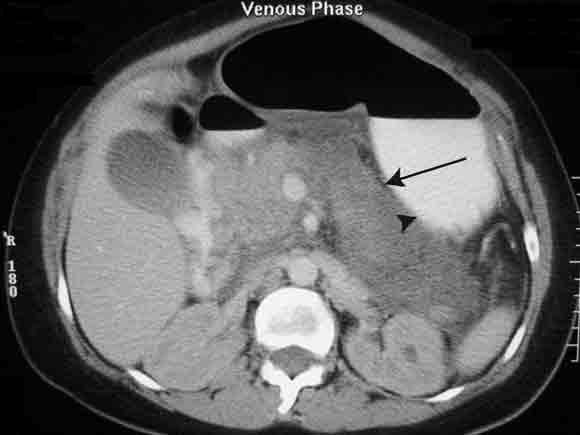

Subsequently, a computed tomography (CT) scan of the woman’s abdomen confirmed acute pancreatitis, with an oedematous pancreas and fluid in the paracolic gutter (Box 1). Her serum parathyroid hormone (PTH) level on Day 2 was suppressed (0.66 pmol/L; RR, 1.3–6.8 pmol/L), with PTH-related protein undetectable (< 1 pmol/L). On Day 7, her serum 25-hydroxy-vitamin D level was inappropriately high (120 nmol/L; RR, 25–108 nmol/L). (On later questioning, she said she had not taken vitamin D supplements.) The level of 1,25-dihydroxyvitamin D was not measured. The serum level of angiotensin-converting enzyme was normal.

Acknowledgement: We thank Dr Jeremy Frank (Department of Diagnostic Imaging, Western Hospital, VIC) for providing the digital image of the abdominal computed tomography scan.